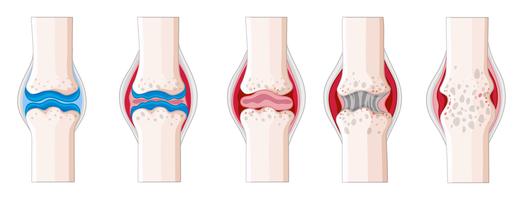

Arthritis affects the musculoskeletal system and specifically the joints. It’s an inflammation of the joints. It’s the main cause of disability among people over 55. Arthritis is a term that covers over 100 medical conditions. Osteoarthritis is the most common form of arthritis and usually affects the elderly.

When someone has arthritis something has gone wrong in the joint depending on the type of arthritis. It could be the cartilage wearing away, lack of fluid, autoimmunity (body attacking itself), infection or a combination of many factors.